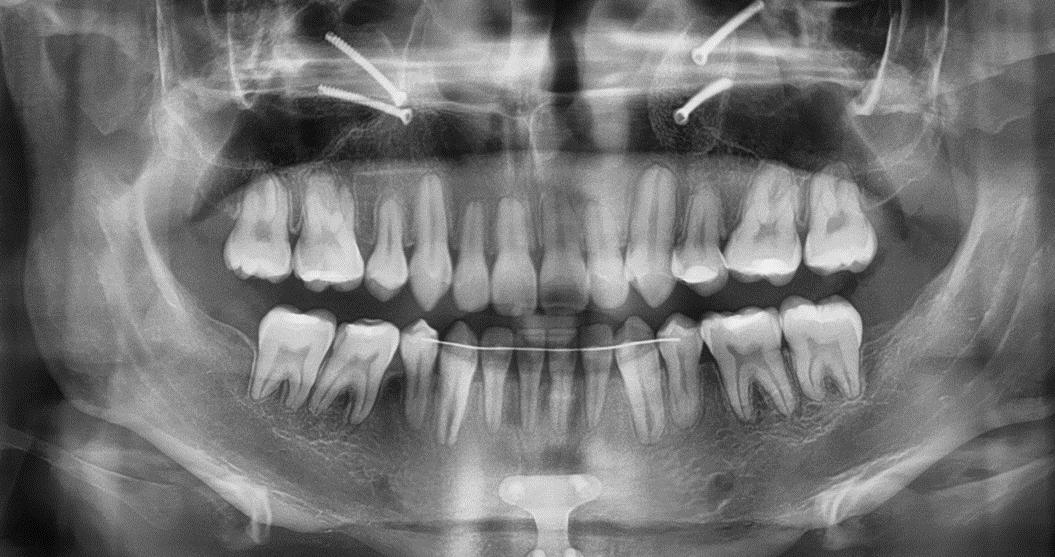

En la radiografía panorámica (Figura 3) se observan las raíces cortas de los incisivos centrales y del O.D. 22, además de los terceros molares superiores e inferiores en formación.

Figura 3. Radiografía Panorámica inicio.